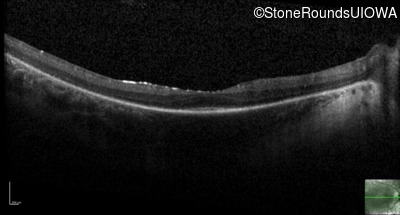

Optical Coherence Tomography - Right - 20/100 -2

Exemplar / OCT Stack